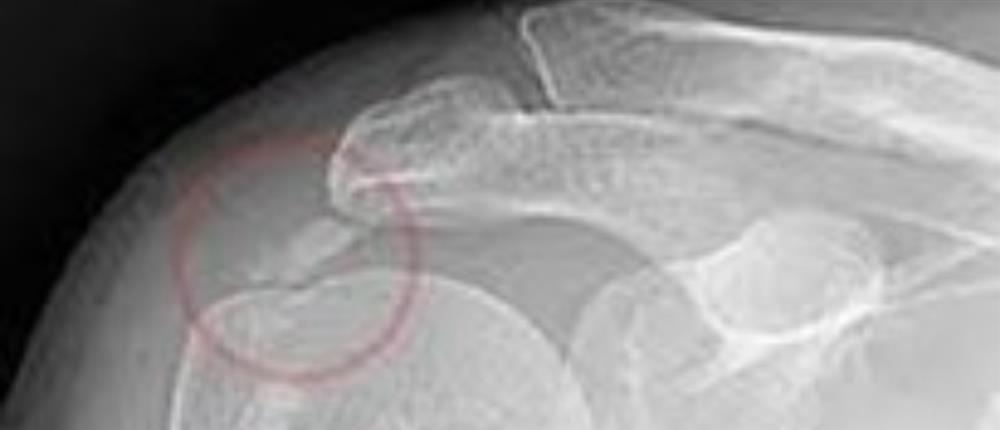

Εικόνα με ακτινογραφία ώμου στην οποία εμφανίζεται η ασβεστοποίηση.

Η διάγνωση, γίνεται κλινικά και επιβεβαιώνεται με ακτινολογικό έλεγχο, ενώ σημαντικές πληροφορίες προσφέρουν τόσο το υπερηχογράφημα, όσο

και η μαγνητική τομογραφία (MRI) για ανακάλυψη συνοδών βλαβών του ώμου όπως εκφυλίσεις και ρήξεις τενόντων.